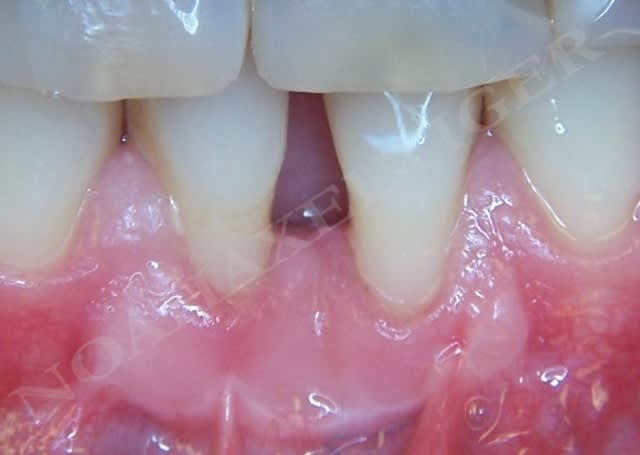

Img 8465 fqhxid - Eugenol

.

Initial ctkv65 - Eugenol

Lit receveur loll9i - Eugenol

Mise en place du greffon conjonctif ejn6xx - Eugenol

Sutures e7ixmz - Eugenol

Zone de prelevement palatin wngjgr - Eugenol